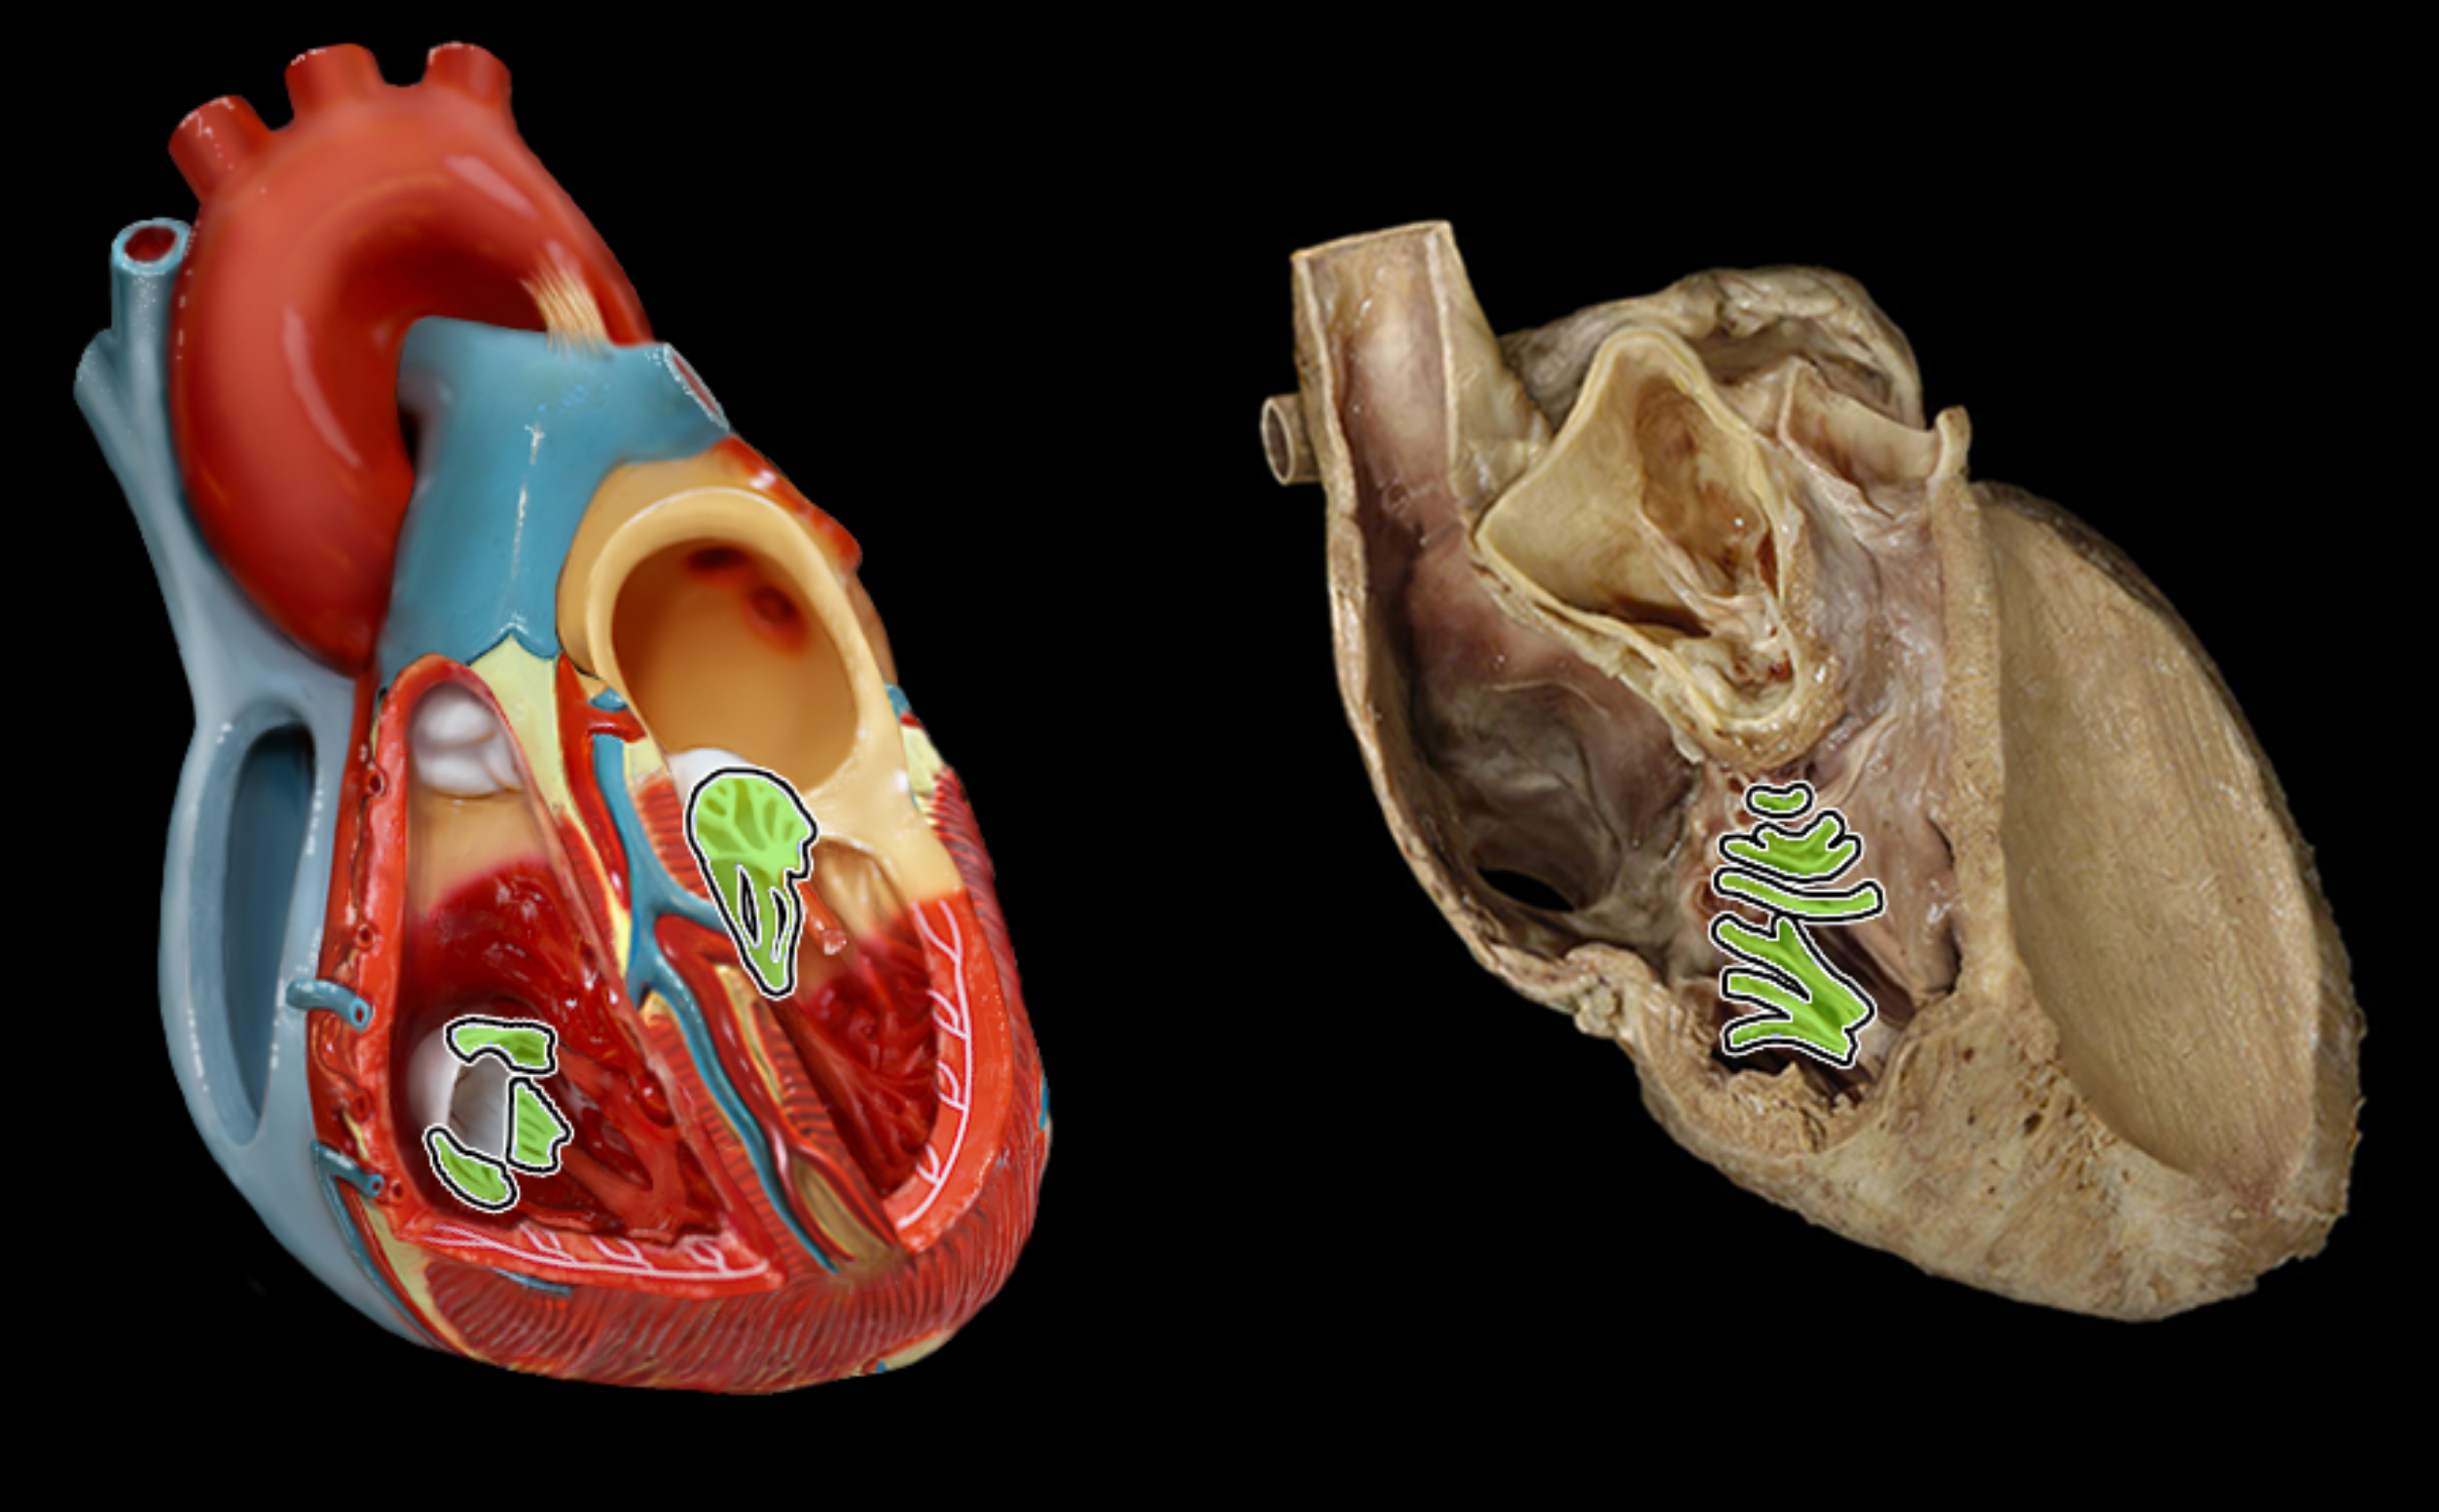

Chordae tendineae

Papillary muscle